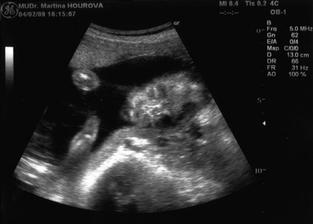

23/4 - II. screaning - cekame obrika 🙂 - podle UTZ vazime 2068g a obvod hlavicky je 34cm. Brisko jsme meli taky pekne napapany 😉 a uplne bylo videt, jak ma nase zlaticko naducane tvaricky, holt mu chutna stejne jako mne 😉. 31+6 a 11 kg navic, +30cm v pase 😉.

22/5 - posledni kontrola u nasi pani doktorky dopadla nasledovne, malem jsem tam omdlela 🙂. Pani dr. nam delala posledni utz, kde jsme zjistili, ze Vojtisek se s rustem umoudril a dostal se do rozmeru normalniho miminka 🙂. Mame 2568g a ocekavana porodni vaha je 3,5kg. Chtela nam i natocit monitor, ale udelalo se mi na vysetrovacim stole spatne, takze z toho seslo a na me se muselo otevrit okno. Tlak trosku vyssi oproti normalu 130/85.